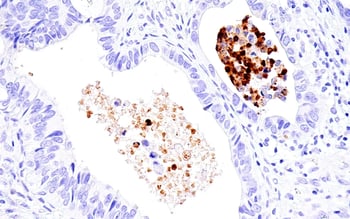

| Immunohistochemical analysis of paraffin-embedded human endometrioid adenocarcinoma using IL-8 (E5F5Q) Rabbit Monoclonal Antibody #94407. | IHC analysis of paraffin-embedded human cervical carcinoma using MMP-2 (D4M2N) Rabbit Monoclonal Antibody #40994. |